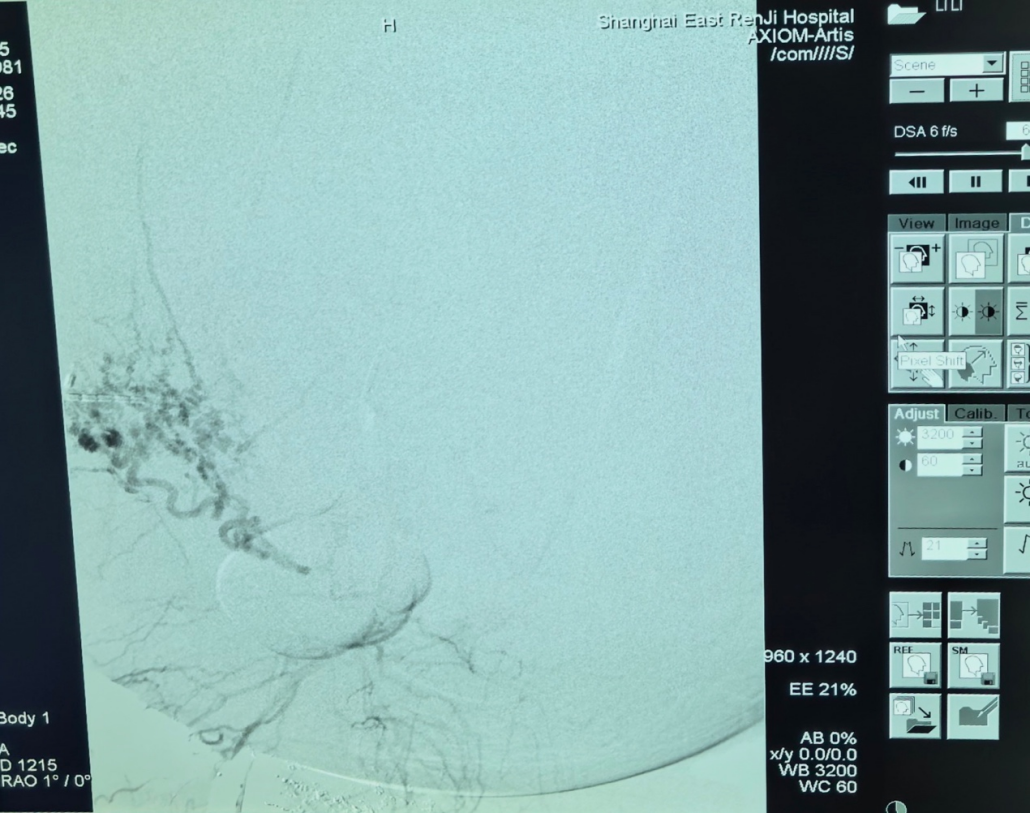

第一棒交给肿瘤介入科主任张学彬。在DSA(数字减影血管造影)的精确疏导下,张学彬凭借娴熟的时代,顺利找到并栓塞了肿瘤的多支润泽动脉,为后续手术撤消了最大的“路障”。